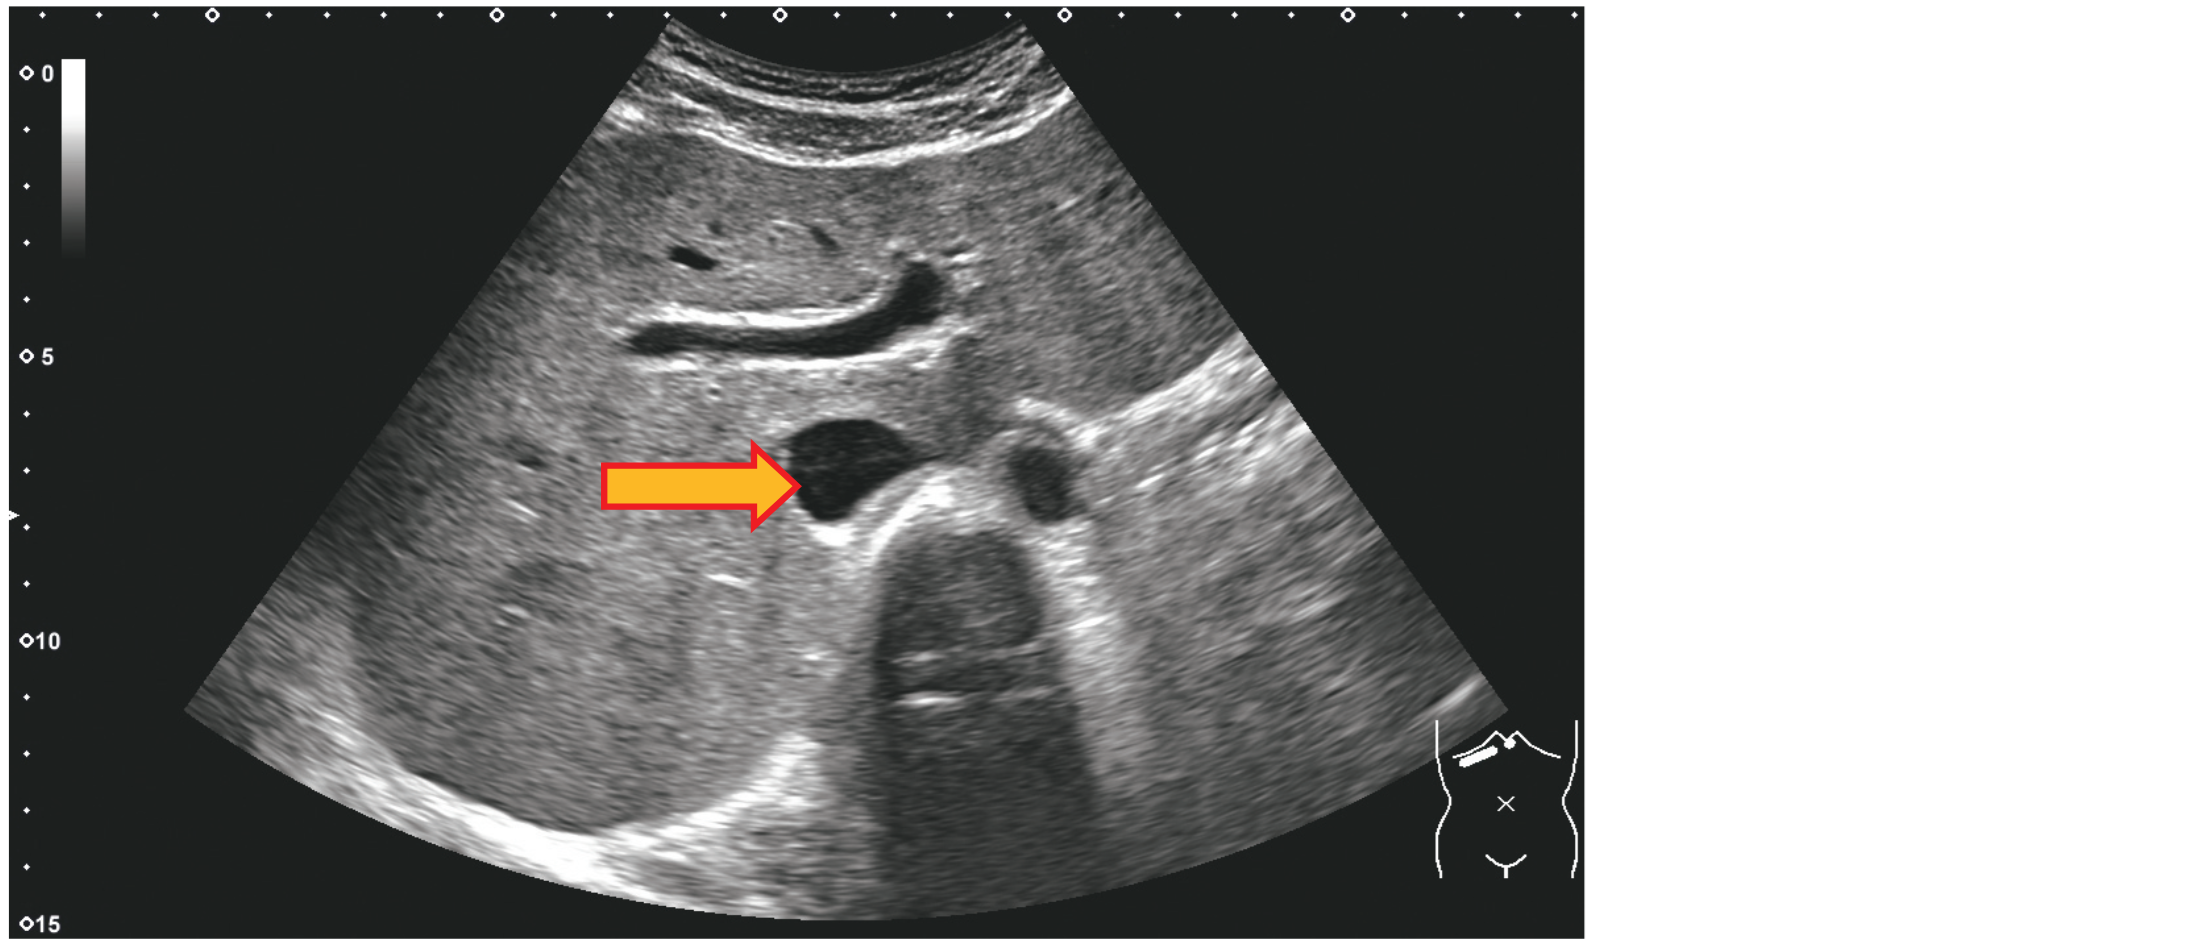

心窩部斜走査による上腹部の超音波像を示す。

矢印で示すのはどれか。

1. 肝動脈

2. 大動脈

3. 下大静脈

4. 肝外胆管

5. 門脈本幹